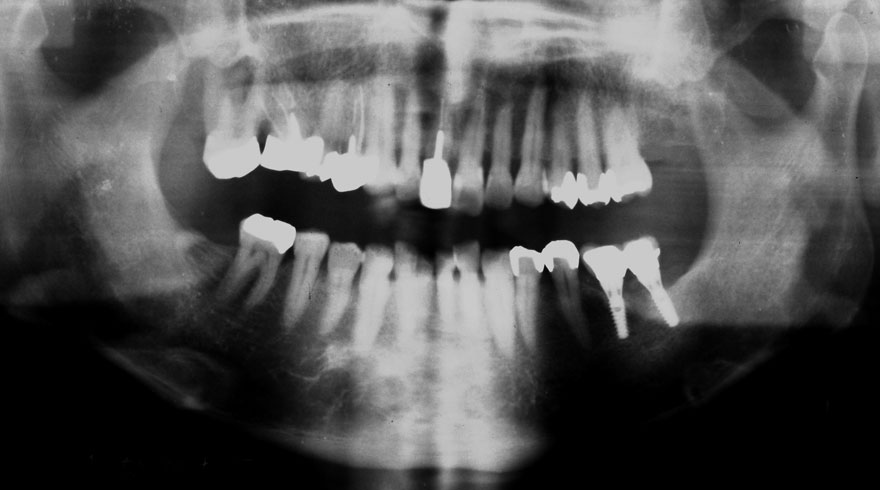

初診時 51歳 男性 平均歯槽骨喪失量:2.83mm

河田歯科医院

21年後 72歳

平均歯槽骨喪失量:2.51mm

21年間再生量:+0.32mm

年間再生速度:+0.015mm

(ケア頻度:1.20ヵ月ごと)